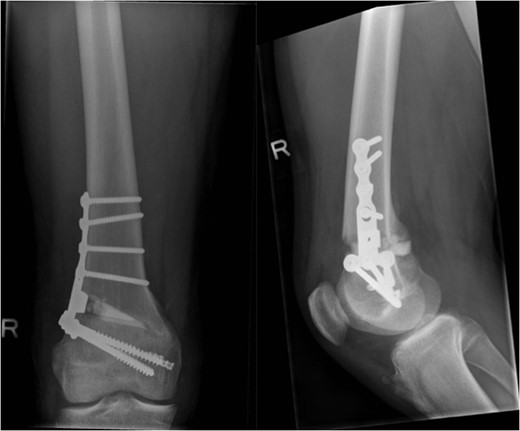

The patient's initial management was non-operative with a period of knee protection with a range of movement brace and intensive rehabilitation. Approximately 3 months after the index injury he returned to competitive football but shortly after his return sustained a further valgus injury and despite further conservative treatment was unable to return to sport. He was referred to our service with ongoing instability symptoms. Upon clinical assessment we noted an asymmetric valgus alignment of the knee and abnormal laxity of the MCL. Radiographic investigations revealed an abnormality of the lateral distal femur and alignment radiographs confirmed the valgus mal-alignment with abnormal opening of the medial tibio-femoral joint space on single-leg stance radiographs (Figs 2–4). We obtained the patient's MRI scan and reviewing this with Radiology colleagues revealed subtle changes of increased lateral femoral physis fluid density on T-2 weighted images consistent with a Salter Harris Type V injury (Fig. 5).

The patient was counseled as to the nature of their injury and the likelihood of ongoing instability and potential for early degenerative change with conservative management. The deformity and instability were successfully treated with an opening distal femoral osteotomy combined with surgical plication of the MCL (Figs 6 and 7). At the time of reporting, 2 years following surgery, the patient has successfully returned to playing competitive football without symptoms of instability. The metalwork remains in situ.